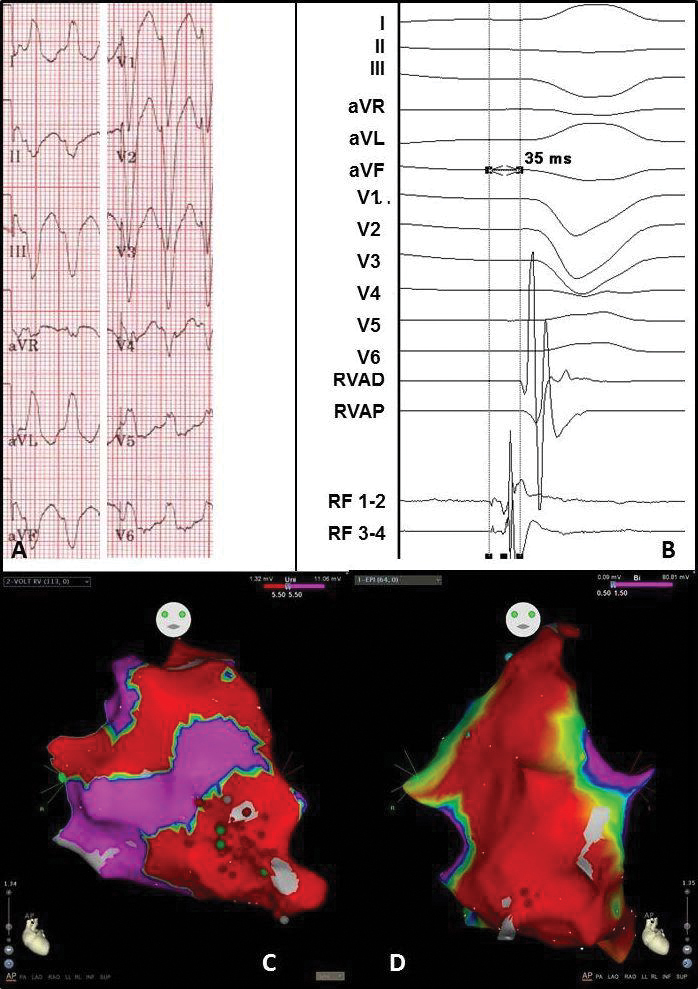

Figure 5 Electrocardiogram and electro-anatomical maps of case 3

A. Twelve-lead electrocardiogram showing a ventricular tachycardia (180bpm) with left bundle branch block morphology and superior axis, suggesting origin in the right ventricle (RV) free wall.

B. Recording obtained in sinus rhythm during the procedure showing prepotentials. RVAD/P = right ventricular apex distal/proximal, RF = radiofrequency.

C. Anterior-posterior (AP) view of the unipolar endocardial voltage map showing a low voltage area at the apex and RV free wall (area 14 and 18). Red dots = RF applications

D. Anterior-posterior (AP) view of the bipolar epicardial voltage map showing a low voltage area at basically the total apex and RV free wall (area 14 and 18). Red dots = RF applications